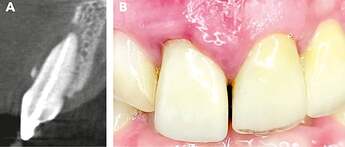

Initial clinical situation. The sectional image of the CBCT, along with the recession on tooth 11, reveals a class III defect according to Kim et al. [3]. The mucosa appears inflamed, and an extensive loss of the buccal alveolar wall is visible

Final situation. After 4 months, when the surgical site was reopened (Figure J), a completely regenerated alveolar ridge was revealed. The alveolus showed complete radiological regeneration (Figure K), allowing for straightforward implant placement. Figure L illustrates the final prosthetic restoration with irritation-free mucosa conditions after one year